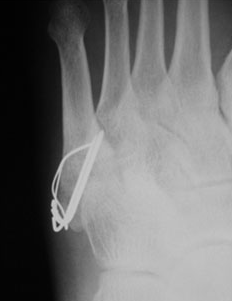

3. 제5중족골 골절

중족골은 발의 5개로 이루어진 뼈로 몇 번째 뼈가 골절되느냐에 따라 앞에 숫자가 붙습니다. 제5중족골은 새끼발가락 쪽 뼈에 해당합니다. 보행 중 바닥의 단차로 안쪽으로 발이 비틀렸을 때 자주 일어나며, 뼈의 어긋남이 없는 골절은 깁스로 고정하거나 압박붕대로 고정하는 등의 보존치료등을 시행하며, 어긋남의 편차가 크다면 강선과 와이어 등으로 고정하는 수술을 하게 될 가능성이 있습니다.